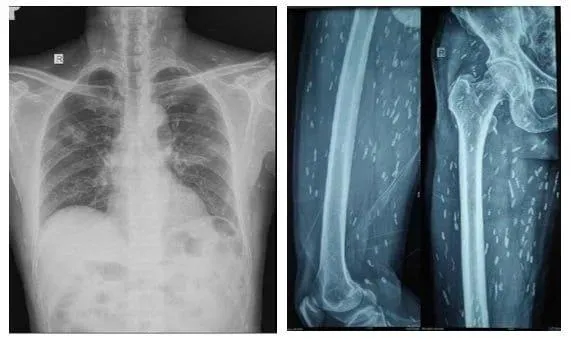

Để tầm soát tổn thương ở cơ quan khác, người bệnh được chụp X- quang xương đùi, CT-scan ngực, phát hiện vô số nang sán dải còn sống hoặc đã bị vôi hóa, “ẩn nấp” trong não, nhu mô phổi, trong da và cơ trên toàn bộ cơ thể.

"Bệnh nhân được chẩn đoán viêm não do nang sán dải lợn và nhiễm nang sán dải ở đa cơ quan, nổi bật nhất là ở não, mô dưới da và ở cơ. Sau khi điều trị bằng thuốc chống ký sinh trùng, chống viêm, phòng ngừa co giật, bệnh nhân hồi phục tốt và được xuất viện”, BS Trần Thanh Hùng thông tin.